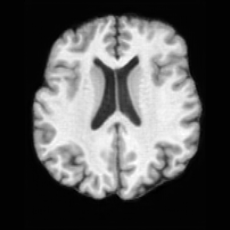

Conditional Generation. Fig. 4 (b) shows conditional generation results given a lesion mask. Conditioned on a single lesion mask, USB can generate an unlimited brain image samples that embed the specified lesion, producing diverse anatomical appearances while maintaining faithful pathological localization. As illustrated by the samples along each row, the generated pathological images exhibit variations in intensity, texture, and local tissue response.

In Tab. 1, we present the first quantitative benchmark evaluation of both generation tasks. For the unconditional generation task, we generated 256 paired lesion–brain samples for each lesion type (stroke and WMH). For the conditional generation task, we used masks from the ATLAS and ISLES test sets as stroke lesions, and masks from the ADNI test set as WMH lesions. Notably, for each lesion type, the unconditional generation achieved superior quantitative performance, highlighting that the paired diffusion mechanism effectively generates coherent lesion-brain pairs through joint modeling between USBbrain and USBlesion. Additional generation results are provided in Suppl. A.